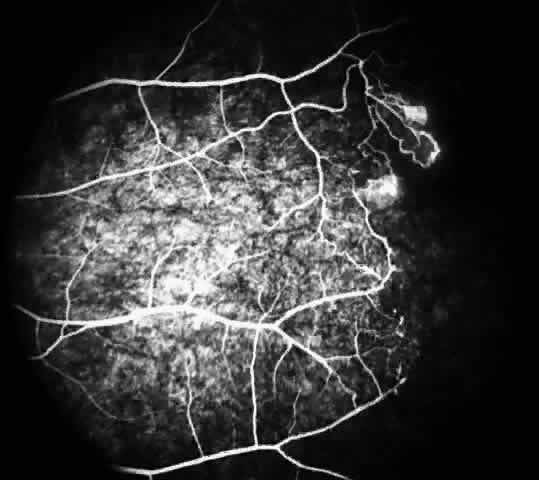

Fluorescein angiography remains the best method of identifying these peripheral retinal changes and documenting the presence of neovascularization.19

The occluded arterioles may be invisible or may have a “silver-wire” or chalk-white appearance, as first described by Goodman and colleagues39 (Fig. 21). Fluorescein angiography may demonstrate an abrupt complete occlusion at the interface between peripheral nonperfused and posterior perfused retina. Frequently, this occlusion will take place just distal to a branching vessel, giving the appearance of a freshly pruned rose bush. The nonperfused anterior peripheral retina will have a grayish brown appearance and on fluorescein angiography will appear blurred without clearly defined fundus markings.

STAGE II: PERIPHERAL ARTERIOLAR-VENULAR ANASTOMOSES. Following occlusion of the terminal arterioles, anastomotic channels form to channel the blood from the occluded arteriole to the nearest venules. These anastomoses form at the interface between the perfused and nonperfused retina. Most likely, they are dilated preexisting capillaries rather than new vessels, since they do not leak on fluorescein angiography. The redirection of blood flow is probably due to hydrostatic forces (Figs. 22 and 23).

STAGE III: PRERETINAL NEOVASCULARIZATION (PROLIFERATIVE SICKLE RETINOPATHY). “Sea fan”-shaped neovascularization typically develops on the venular side of an arteriolar-venular anastomosis, mimicking the normal development of retinal capillaries (Fig. 24).125 A lowered oxygen tension and angiogenic factors released on the venular side may be the stimulus for neovascular growth.125,126 In most instances, the direction of growth is toward the ora serrata, from the perfused retina toward the nonperfused retina. Presumably, this represents an abortive attempt to revascularize the nonperfused retina, initiated by vasoproliferative factors.

The characteristic neovascular lesions of PSR are called sea fans because they resemble the marine invertebrate Gorgonia flabellum.70 They tend to occur more commonly in the temporal periphery, but they have been reported to occur in the temporal macula in the presence of extensive nonperfusion.130,133 Initially they grow on the surface of the retina, but they often become elevated into the vitreous and adhere to a partially detached posterior hyaloid.114 It may be difficult to visualize small sea fans ophthalmoscopically; however, fluorescein angiography clearly demonstrates leakage of dye into the vitreous (Fig. 25). The feeding arteriole is usually more tortuous than the draining venule (Fig. 26). Early on, the neovascular lesion is fed by a single arteriole and drained by a single venule, but with time, additional arterioles and venules become arborized within the lesion (Fig. 27).129 Growth of the sea fan often occurs circumferentially, rather than radiallyÜmh- 1Ý, toward the ora serrata. Progressive circumferential growth may lead to neovascular lesions extending around the entire periphery. As it matures, a white fibroglial mantle often covers the neovascular tissue (Color Plate 2B).